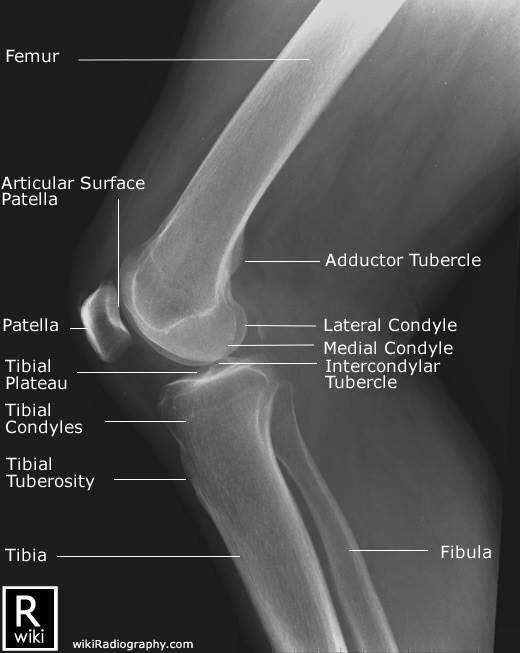

Las radiografías, generalmente llamadas rayos X, producen imágenes como sombras de huesos y ciertos órganos y tejidos. Las radiografías son muy buenas para detectar problemas óseos. Pueden mostrar algunos órganos y tejidos blandos; sin embargo, la MRI y la CT suelen crear mejores imágenes de los mismos. Aun así, las radiografías son rápidas, fáciles de obtener y menos costosas que los otros estudios, por lo que se pueden usar para obtener información rápidamente.

Un tubo especial dentro de la máquina de rayos X emite un haz de radiación controlada. Los tejidos del cuerpo absorben o bloquean la radiación en diferentes grados. Los tejidos densos como los huesos bloquean la mayor parte de la radiación, pero los tejidos blandos, como la grasa o los músculos, bloquean menos radiación. Después de pasar por el cuerpo, el haz alcanza una pieza de un fragmento de película o un detector especial. Los tejidos que bloquean altas cantidades de radiación, como los huesos, aparecen como áreas blancas en un fondo negro. Los tejidos blandos bloquean menos radiación y aparecen en tonos de gris. Los órganos que contienen principalmente aire (como los pulmones) aparecen en negro. Los tumores son por lo general más densos que el tejido que los rodea, por lo que suelen verse en tonos grises más claros.